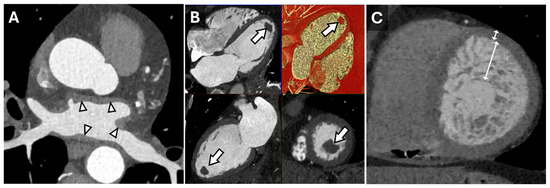

Cardiac CT is well-suited for the evaluation of morphologic features, such as wall thickness and chamber dimensions, given its excellent spatial resolution and volumetric acquisition. It is worth noting that most CT coronary angiography is performed during end-systole or mid-diastole, which may result in an overestimation of wall thickness and underestimate end-diastolic volumes []. Additional features, such as atrial wall thickening, left ventricular thrombus, or non-compaction, can be identified regardless of the cardiac cycle phase (Figure 1) []. Thrombus detection, in particular, is often more reliable with CT than echocardiography, as it appears as a filling defect in a contrast-filled chamber. Beyond cardiac morphology, CT can reveal extracardiac findings that may provide broader diagnostic insights. For instance, bilateral hilar adenopathy, visible on cardiac CT, may suggest sarcoidosis, expanding the diagnostic perspective beyond cardiac pathology (Figure 2).

Figure 1. Cardiac Findings and CT Imaging. Axial reconstruction from a contrast-enhanced cardiac CT (A) demonstrating irregular left atrial wall thickening (arrowheads) reflecting amyloid deposition in the setting of cardiac amyloidosis. Multiplanar (HLA, VLA, SAX, 3D) diastolic images (B) from a contrast-enhanced cardiac CT in a patient with a left ventricular apical thrombus (arrows). Short-axis end-diastolic image from a contrast-enhanced cardiac CT in a patient with myocardial non-compaction (C) demonstrating very prominent trabeculation of the mid-apical left ventricle with an increased ratio of non-compacted to compacted myocardium measuring >> 2.3:1 (double-headed arrows).